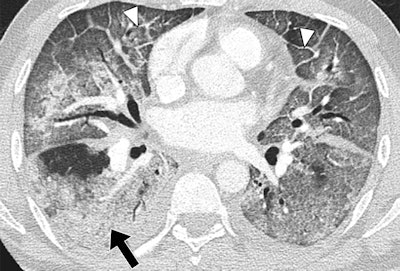

Lower-lung CT image shows more extensive and confluent basal abnormalities, with right lower lobe consolidation (arrow) and bilateral smooth interlobular septal thickening (arrowheads).Several recent publications have examined MERS, but it has mostly been in nonimaging medical literature, and descriptions of the imaging features are sparse, especially in CT, the study authors wrote. What descriptions exist characterize the infection simply as bilateral patchy or extensive opacities (AJR, June 11, 2014).